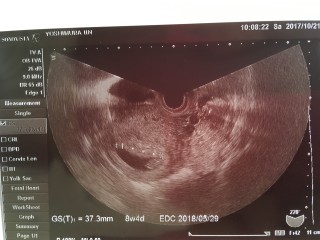

出産予定日を決める健診でした。 結果、最終生理日の計算通り8週4日で出産予定日を計算することに! エコーは大きめに計算でたから、早くなるかと期待しましたが、目安だから気にしないことにしました( ̄ー ̄)ノ"